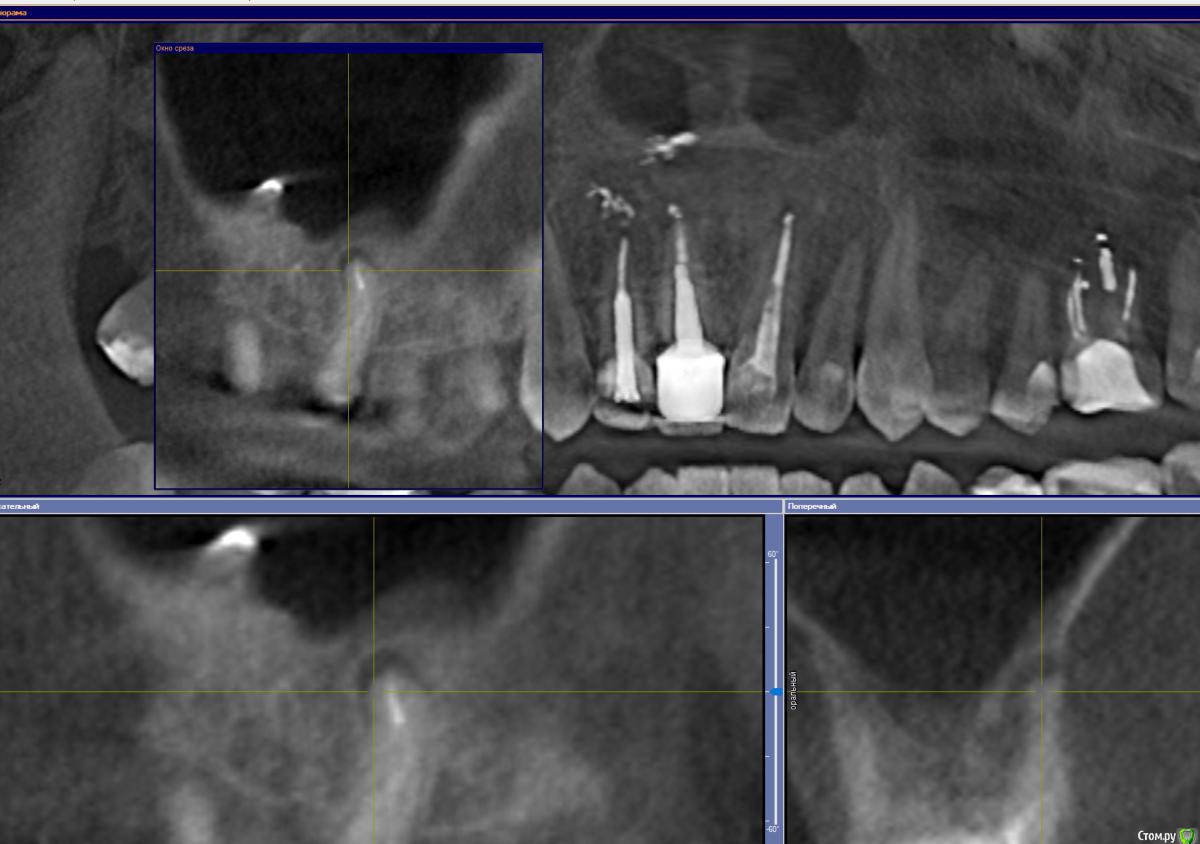

GoldJoker Опубликовано 11 декабря, 2017 Поделиться Опубликовано 11 декабря, 2017 Сломан инструмент/Киста - Удалять, резекция, пробовать достать инструмент. 16 зуб. Шестерка.Говорят при попытке достать можно протолкнуть инструмент. Как считаете пробовать доставать под микроскопом, резекция или сразу удалять?После грипа дискомфорт в десне над зубом, чувствую воспаление. Срезы прикрепил. Ссылка на комментарий

GoldJoker Опубликовано 11 декабря, 2017 Автор Поделиться Опубликовано 11 декабря, 2017 Срезы не информативны, но я за лечениеИнструмент за изгибом думаете достать пробовать? Добавляю срезы. Просто что делать если его выбьют за верхушку корня при попытки достать его ультразвуком?http://joxi.net/V2VvZN4SxPvbO2http://joxi.ru/xAeXqnbIpGl9D2 Ссылка на комментарий